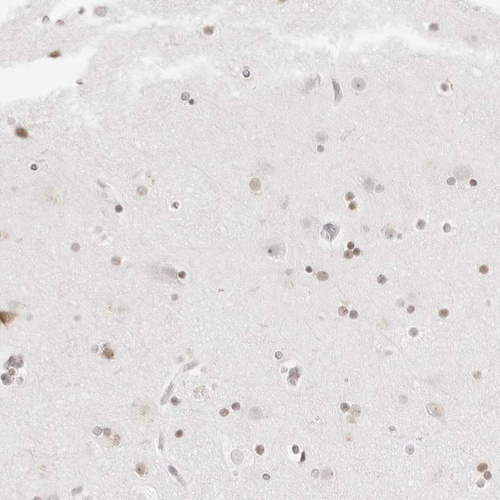

Immunohistochemistry analysis in human testis and cerebral cortex tissues using HPA027573 antibody. Corresponding RCC1 RNA-seq data are presented for the same tissues.